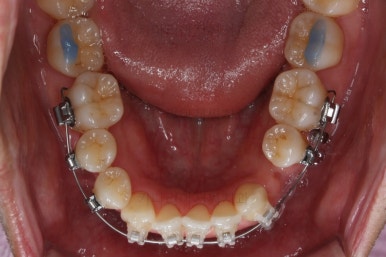

부산비수술교정 키다리아저씨치과에 처음 내원하셨을 당시의 입 안의 모습입니다.

아래 앞니에 결손치아가 하나 있네요. 송곳니-송곳니 사이에 앞니가 4개가 있어야 정상이지만 이 분은 3개에요. 의외로 아래앞니 하나 혹은 두개가 없는 경우가 굉장히 많답니다.

갯수가 맞지 않다보니 치열의 중앙도 맞지 않고 비대칭이 됩니다.

그리고 주걱턱이기 때문에 당연히 아랫니들도 앞으로 나올 수 밖에 없어 윗니보다 앞에 나와있어요.

이를 반대교합이라고 합니다.